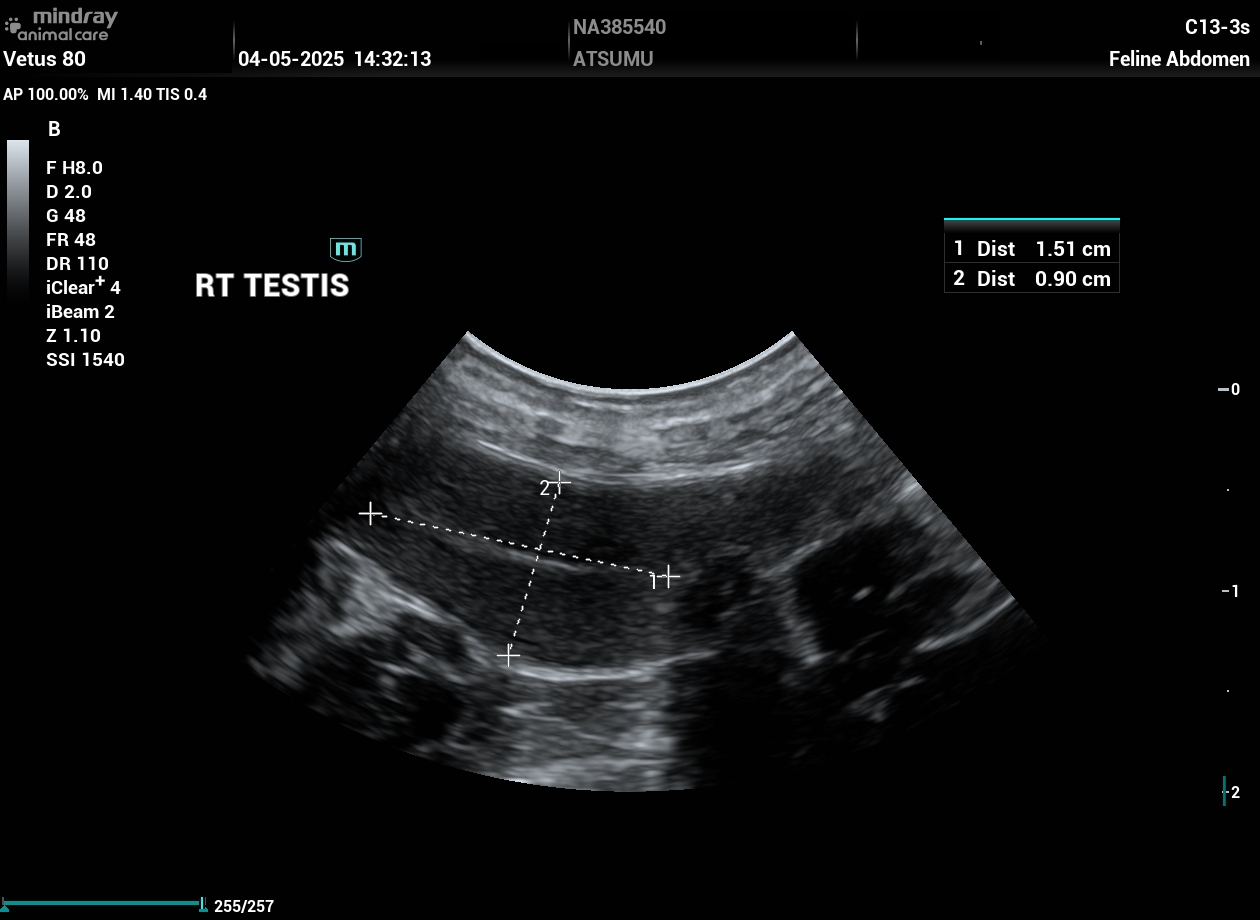

202505041432510004ABD.JPG